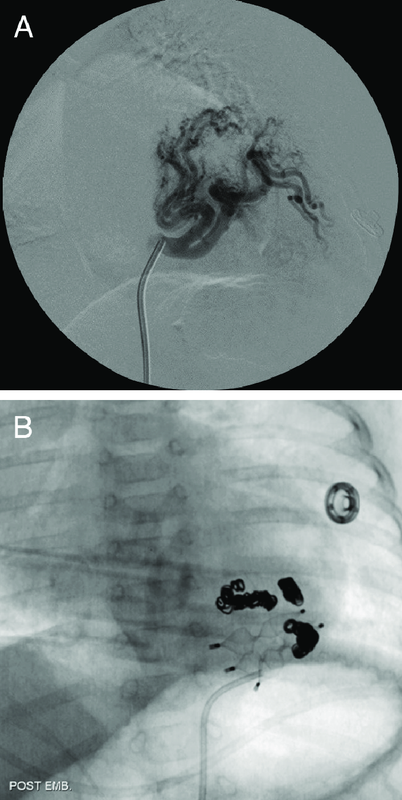

Как проводится химиэмболизация?

Химиоэмболизация проводится врачом – интервенционным онкологом (радиологом) под контролем современного высокотехнологичного рентген-аппарата – ангиографа при помощи введения специальных эндоваскулярных (внутрисосудистых) катетеров и проведения их внутреннего кончика в сосуды питающие опухолевое образование.

Использование современного эндоваскулярного инструментария, позволяет вводить катетер и микрокатетер в самые отдаленные и извитые сосудистые бассейны. После того как внутренний кончик катетера установлен в просвете сосуда питающего опухоль, через наружный конец производится медленное введение химиопрепарата, с последующим закрытием просвета сосудов при помощи введения эмболов. После этого катетер и микрокатетер извлекаются из просвета сосудов.